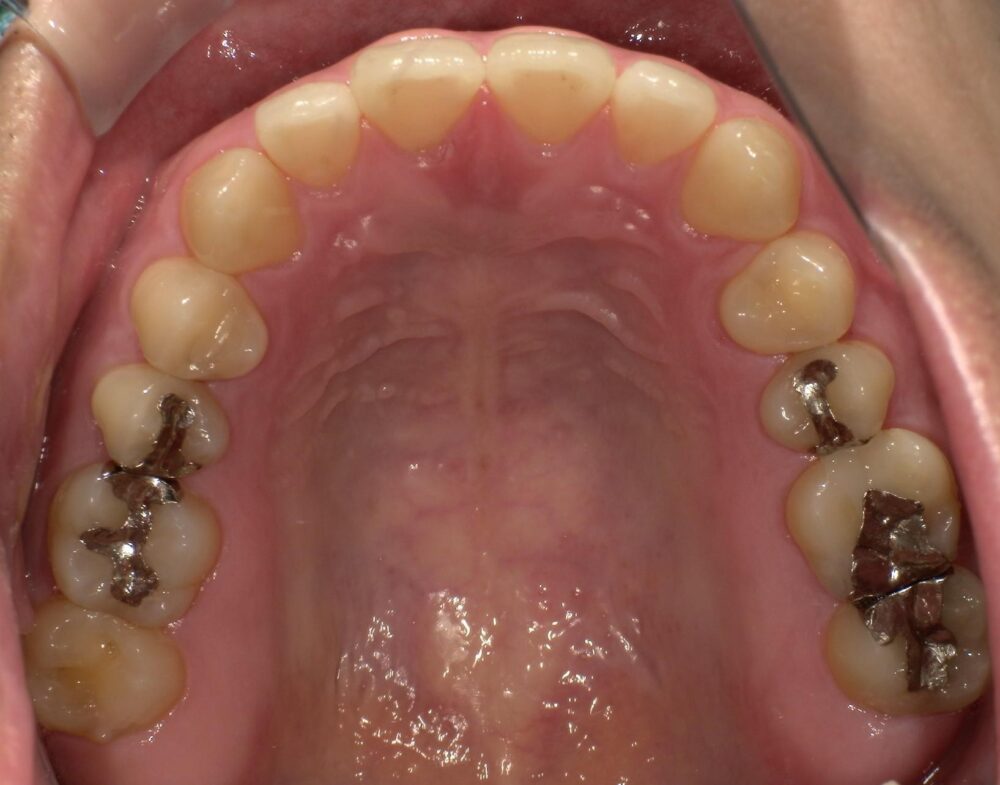

症例3

治療前

| 主訴 | 虫歯を治したい |

|---|---|

| 診断 |

2次虫歯 |

| 治療内容 | 保険CAD インレーによる修復治療 |

| 年齢・性別 |

29歳男性 |

| 治療期間 |

2ヶ月 |

| 治療費用 | 保険に準ずる。 |

| リスク・副作用 | CADの破折、着色 |